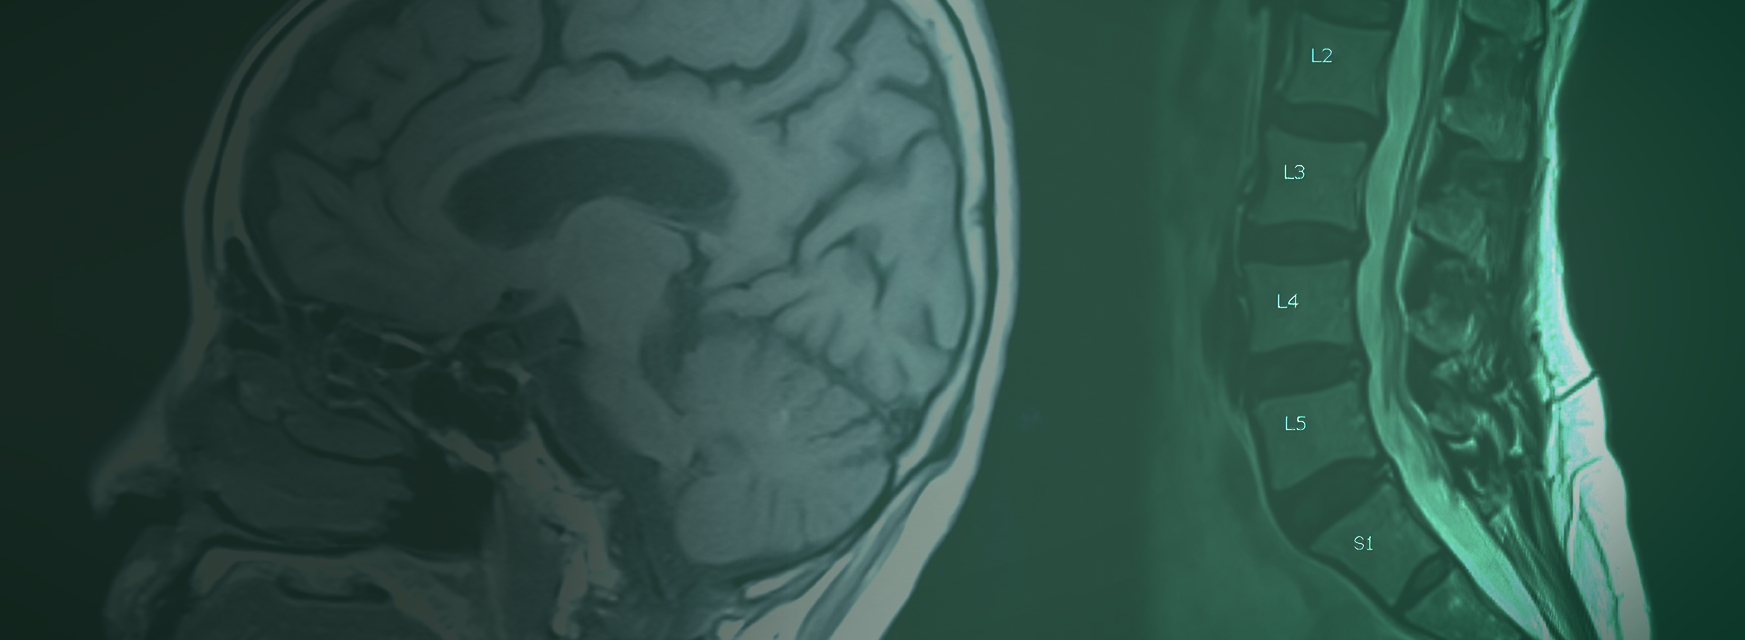

Quando é indicado fazer uma ressonância magnética?

Aqui no blog já explicamos como funciona o exame de ressonância magnética (link). Mas algumas pessoas podem ficar com dúvidas em relação a quando ele é indicado e quais são…

Como funciona o exame de ressonância magnética?

O exame de ressonância magnética é um dos exames mais necessários para a detecção precisa de problemas no corpo humano. No texto de hoje, vamos te falar um pouco sobre…